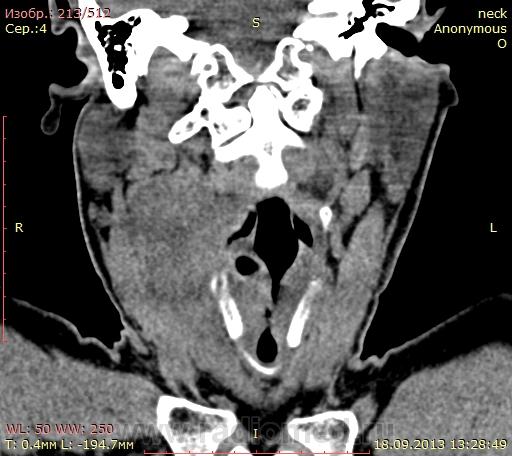

Очень для нас редкое исследование. Помогите, пожалуйста разобраться, откуда что исходит. Из жалоб: осиплость голоса около 5 месяцев. Нигде не лечился, не наблюдался. Сейчас появилась болезненность и припухлость в полчелюстной области справа. Хирург из поликлиники почти пинками к нам в кабинет пригнал. Исследование выполнено только без фонации, он букву ииии вообще не может говорить. Понимаю что все не очень хорошо, но ни сформулировать толком, ни увидеть всю картину не могу.  Вот ссылка на дайком http://yadi.sk/d/nYvyvp2o9UoYJ

Чем могу: это не опухоль гортани, это мягкотканное образование правой половины шеи. А более конкретно не скажу. В пространствах шеи также не силен. Может кто другой скажет?

Так как правильно сформулировать изменения? И какие вообще изменения тут есть? Кроме инфильтрации мышц справа и какого-то жидкостного образования я ничего вразумительного сказать не могу(((

Опухоль в черпало-надгортанной связке справа с распространением на голосовую связку, парагортанное пространство, переднюю комиссуру, склерозирвание и вроде подвывих правого черпаловидного хряща. Дуля справа от подъязычной кости до щитовидного хряща - метастатический узел с распадом.